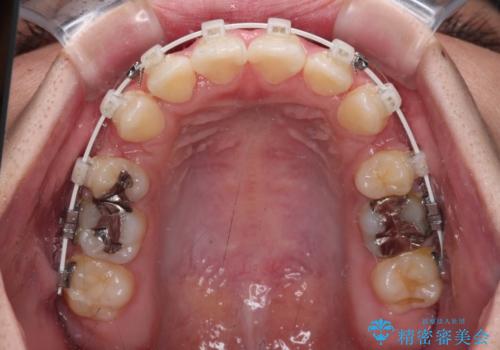

- 口元の突出感を気にして来院された患者様です。

デコボコと口元の突出感が認められたため、上下左右の第1小臼歯4本を抜歯してのワイヤー矯正を行うこととしました。

上顎歯列の横幅が狭く、下顎大臼歯の歯軸が舌側に倒れていたため、急速拡大装置により上顎骨を側方に拡大し、咬み合わせを改善することとしました。

上顎歯列幅を拡大したことで、デコボコを容易に解消することができるようになったため、抜歯により得られたスペースを口元の突出感改善に利用することができました。